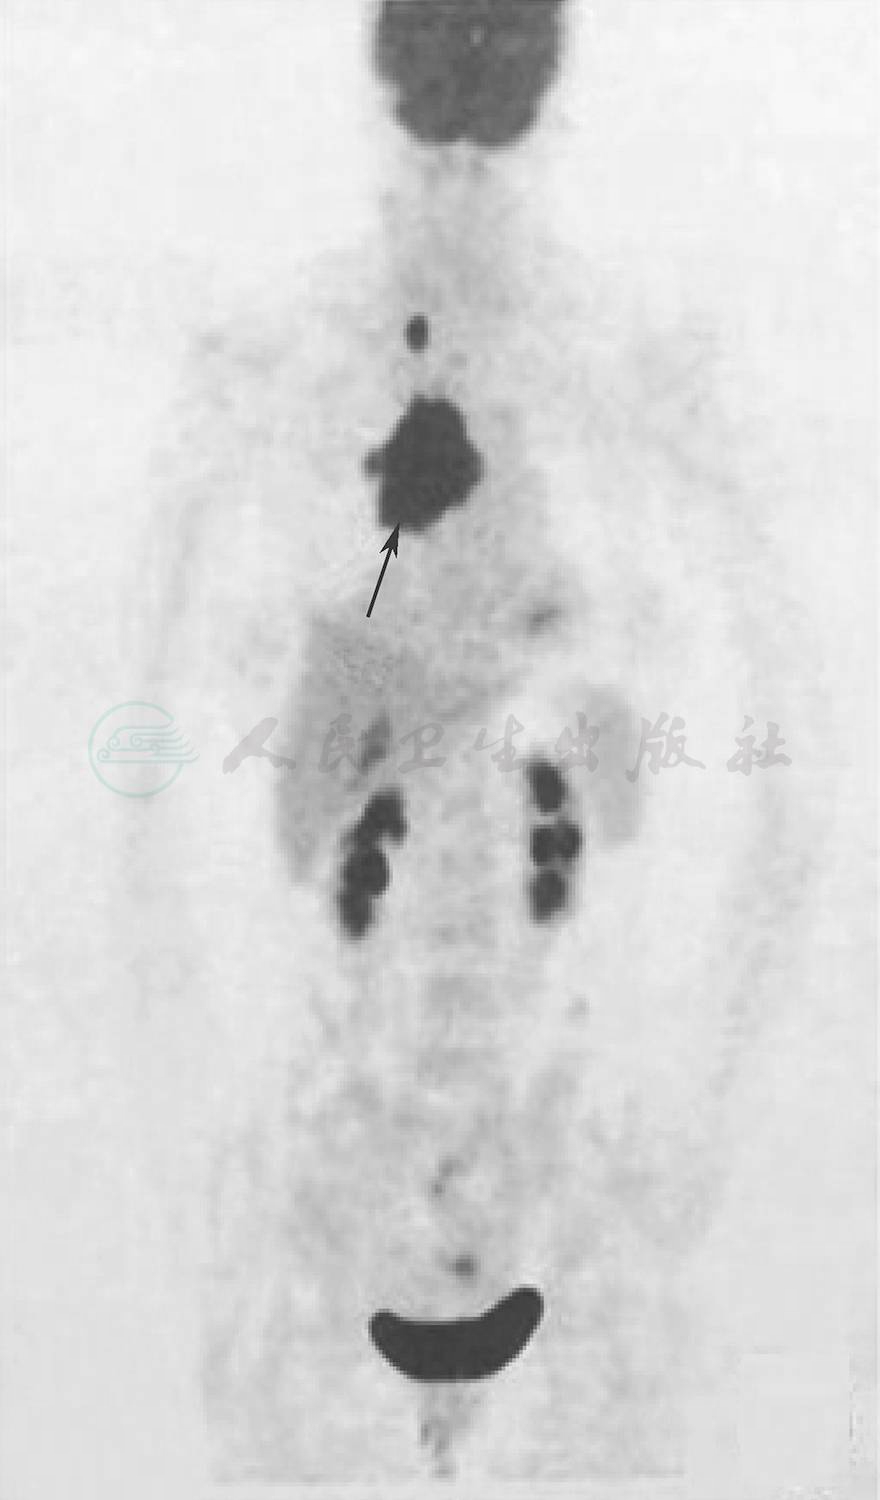

血常规、肝肾功能试验、血脂、胰淀粉酶和脂肪酶、叶酸和维生素B12、甲状腺功能试验,以及血清甲状腺抗体均于正常值范围。动脉血气分析:经皮动脉血氧饱和度(SpO2)95%、动脉血氧分压(PaO2)67.80mmHg、二氧化碳分压(PaCO2)41mmHg,碳酸氢根 24.90mmol/L,pH值7.40。纤维蛋白原5.57g/L(1.80~3.50g/L)、D-二聚体0.98mg/L(0~55mg/L),超敏C反应蛋白(hsCRP)14.18mg/L(0~3mg/L),红细胞沉降率(ESR)67mm/h。风湿免疫学检测:狼疮抗凝物、抗核抗体(ANA)19项、抗可提取性核抗原(ENA)抗体、抗心磷脂抗体(ACA)、β2-糖蛋白1(β2-GP1)抗体、抗中性粒细胞胞质抗体(ANCA)均呈阴性反应。肿瘤标志物:糖链抗原(CA)24227.50U/ml(参考值范围0~20U/ml)、CA19-9 47.10U/ml(参考值范围10~34U/ml);血清蛋白电泳呈阴性。尿常规提示泌尿系统感染。腰椎穿刺脑脊液检查外观澄清、透明,压力>330mmH2O,白细胞计数1×109/L,单核细胞计数1×106/L,蛋白定量、葡萄糖、氯化物均于正常值范围;抗单纯疱疹病毒、巨细胞病毒抗体gM,以及细菌培养、抗酸染色、墨汁染色呈阴性;细胞学检测未见异常。血清和脑脊液抗电压门控钾离子通道(VGKC)抗体、N-甲基-D-天冬氨酸受体(NMDAR)抗体、神经节苷脂GM1抗体、抗Hu、Yo、Ri抗体呈阴性。头部常规MRI和磁敏感加权成像(SWI)未见明显异常;MRV检查下矢状窦未显影,其余无异常。甲状腺和颈部淋巴结超声显示右侧锁骨上窝淋巴结异常增大(第Ⅳ区即颈内静脉淋巴结下组),并可见双侧颈部淋巴结。乳腺超声可见双侧腋下淋巴结,左侧淋巴结部分回声减低。胸腹盆腔CT增强扫描显示纵隔多发性占位性病变,考虑恶性病变;上腔静脉综合征;双侧胸腔积液,双肺受压膨胀不完全;双侧胸膜增厚;心包积液(图1)。全身PET/CT扫描可见右上纵隔代谢异常增高的不规则肿块,堵塞右主支气管和右上叶尖段支气管,呈恶性改变,考虑中央型肺癌伴邻近肺门和纵隔淋巴结转移、右侧锁骨下淋巴结转移;第Ⅳ肝段代谢轻度增高,考虑肿瘤转移;心包积液、双侧胸腔积液;右肺膨胀不完全(图2)。临床诊断:纵隔多发性占位性病变,考虑恶性病变可能;上腔静脉受压;颅内压增高;副肿瘤综合征。入院后予甘露醇125ml和甘油果糖250ml(1次/12h)静脉滴注以降低颅内压,同时予鼻导管吸氧、肠内营养等对症治疗。

图1 患者胸部增强CT扫描

显示纵隔占位性病变压迫上腔静脉(箭头所示)